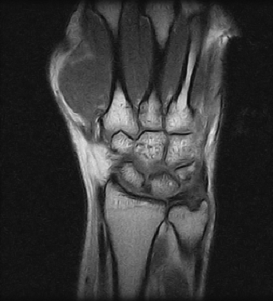

Ressonâncias Magnéticas Punho

Fazemos ressonâncias magnéticas punho utilizando a mais alta tecnologia disponível, ideal até mesmo para pacientes que sofrem com a claustrofobia.